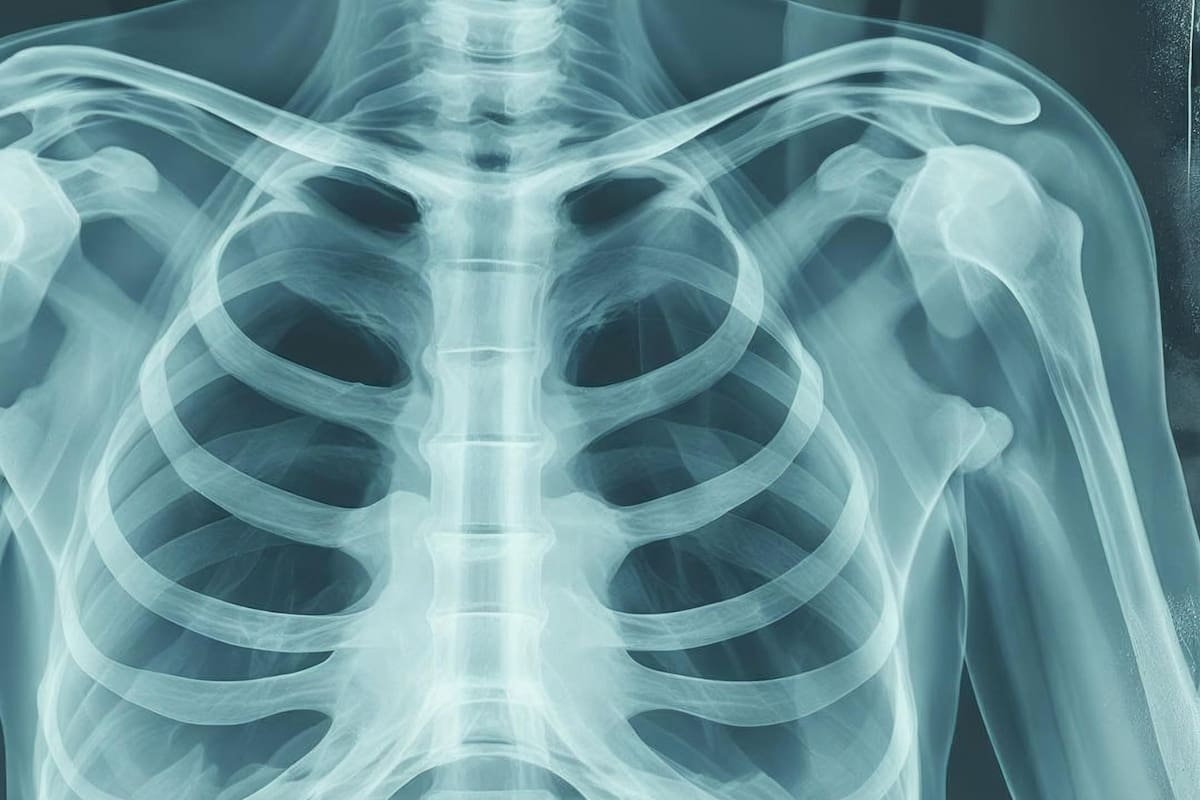

La EPOC se caracteriza por la limitación del flujo de aire y la pérdida de elasticidad pulmonar. Con el tiempo, los pulmones se vuelven rígidos y retienen aire.